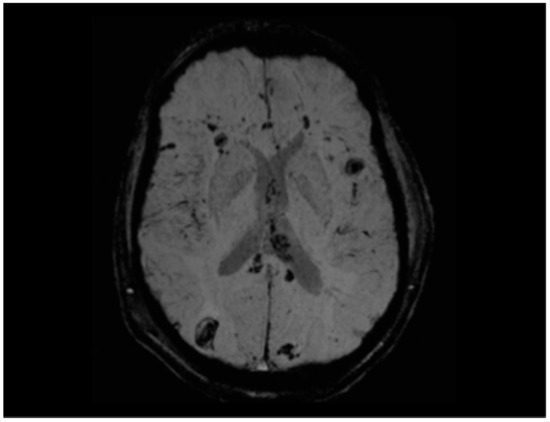

5.3.1. Radiological Findings in Adult DAI

- Abu Hamdeh, S.; Marklund, N.; Lannsjö, M.; Howells, T.; Raininko, R.; Wikström, J.; Enblad, P. Extended anatomical grading in diffuse axonal injury using MRI: Hemorrhagic lesions in the substantia nigra and mesencephalic tegmentum indicate poor long-term outcome. J. Neurotrauma 2017, 34, 341–352. [Google Scholar] [CrossRef]

- Tjerkaski, J.; Nyström, H.; Raj, R.; Lindblad, C.; Bellander, B.M.; Nelson, D.W.; Thelin, E.P. Extended analysis of axonal injuries detected using magnetic resonance imaging in critically ill traumatic brain injury patients. J. Neurotrauma 2022, 39, 58–66. [Google Scholar] [CrossRef] [PubMed]